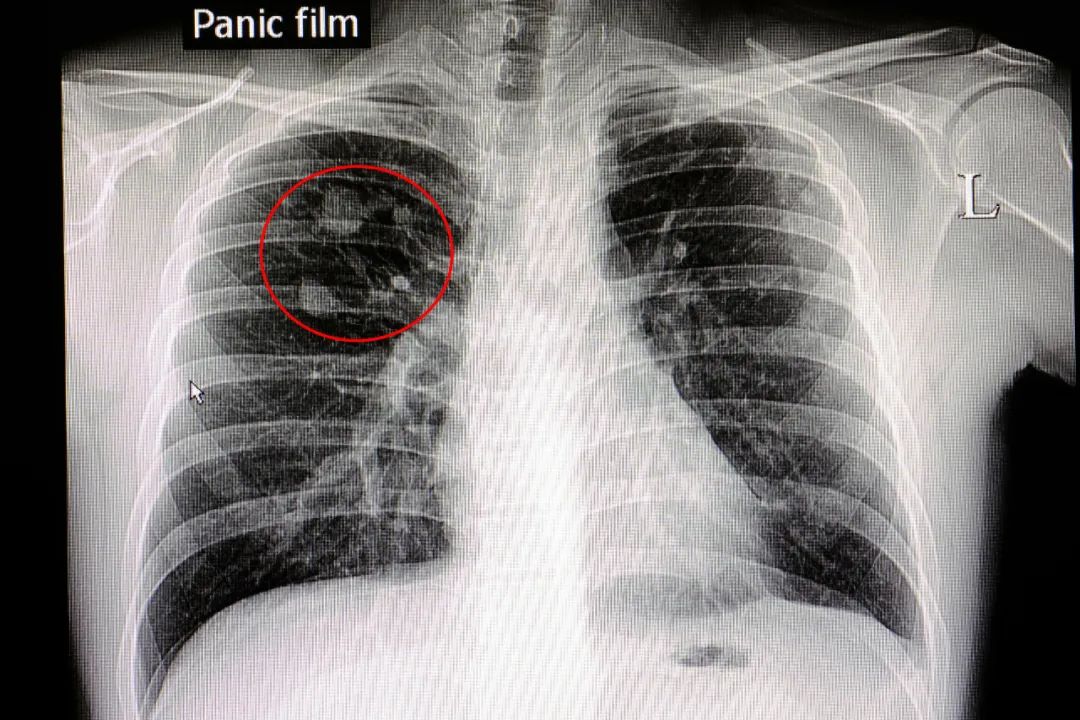

02肺结节

肺结节≠肺癌!看到“肺结节”字样也不用过度紧张,因为大多数的肺部结节是由良性疾病引起,是以前患肺炎、肺结核留下的疤。

雾霾粉尘微小颗粒吸入肺,也可以引起局灶炎症形成肺结节。

肺结节中肺癌的比例很小,90%以上是良性的,恶性的只有 1.2%左右。

小于8毫米肺结节: 肺癌的概率不到 1%,因此,并不需要太过担心。

直径在 6~8 毫米之间的肺结节: 肺癌概率在 0.5%~2%。

直径大于 8 毫米的肺结节: 肺癌概率大于 3%。

过多的担忧和频繁的X线、CT检查反而会促进结节癌变,中医药调理治疗可以提前介入调控。

肺结节处理的三个层面:极少手术、多数观察、大多数不手术。肺结节大都是多发性的,手术不手术都需要中医药调理。